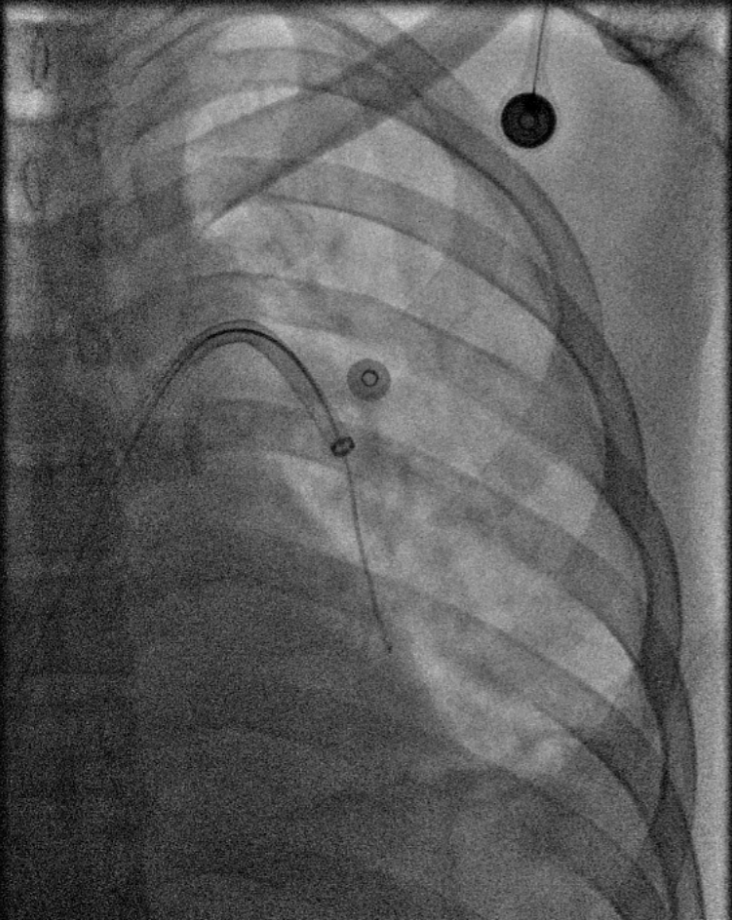

术中导管抽吸血栓、支架取栓